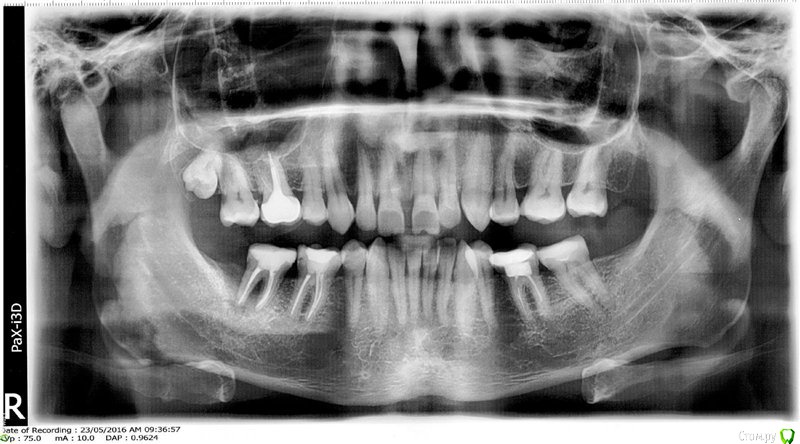

Slava76 Опубликовано 6 октября, 2016 Поделиться Опубликовано 6 октября, 2016 Добрый день!Сейчас планирую ставить имплант вместо удаленного нижнего правого жевательного зуба (на приложенном снимке он еще есть) и коронку на соседний зуб (писал подробно об этом в другой теме http://forum.stom.ru/topic/33696-vmesto-odnogo-zuba-dva-implanta/). У меня не правильный прикус, верхние зубы сильно закрывают нижние, в результате чего зубы стачиваются. Брекеты ставить не хочу. Врач предложила мне на другие два нижних жевательных зуба поставить тоже коронки. Коронки она хочет чуть приподнять (с ее слов буквально на микроны), тем самым прикус чуть-чуть приподнимется. С ее слов пломбы постепенно стачиваются. В результате прикус у меня опустится еще ниже и стачивание передних зубов будет происходить быстрее. Коронки на нижних жевательных зубах не позволят прикусу опускаться ниже и тем самым, передние зубы мне прослужат дольше. Завтра мне уже идти на лечение. А я до сих пор не уверен до конца нужно ли делать коронки на два других зуба, которые меня сейчас совершенно не беспокоят. В предыдущей моей теме, на которую выше давал ссылку, один из врачей мне этого делать не рекомендовал. Хотелось бы услышать мнение врачей в профильной ветке форума.P.s. Плюс, врач сказала что нужно будет перелечивать каналы, что тоже не очень хотелось бы делать. Ссылка на комментарий

Slava76 Опубликовано 6 октября, 2016 Автор Поделиться Опубликовано 6 октября, 2016 данный раздел требует больше информации http://forum.stom.ru/topic/4655-patcientam/Выкладываю свои селфи, которые пришлось сделать прямо на рабочем месте Ниже ссылка на КТhttps://cloud.mail.ru/public/3L7m/pRob6ScpT Ссылка на комментарий